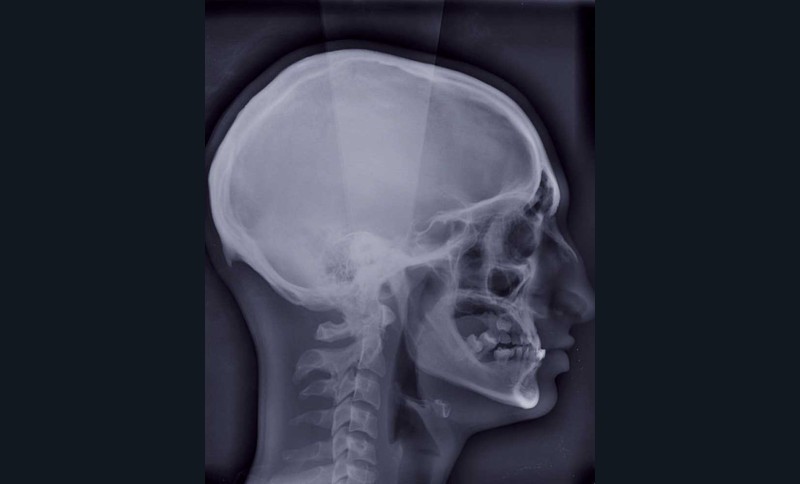

En cas d’hypo-divergence, qu’il s’agisse d’une classe II ou d’une classe III, la mandibule est stabilisée après avoir déterminé « l’espace libre d’innoclusion » (free way space) à l’aide d’une cale radio-opaque ou radio transparente (fig. 2 à 5).

Les données natives en format DICOM sont ensuite traitées (phase de segmentation) :

– suppression des artefacts ;

– élaboration des images 3D en isolant des différents constituants anatomiques : crâne et maxillaire, mandibule, dents, dispositifs d’orthodontie, implants endo-osseux et prothèses conjointes éventuelles, etc.